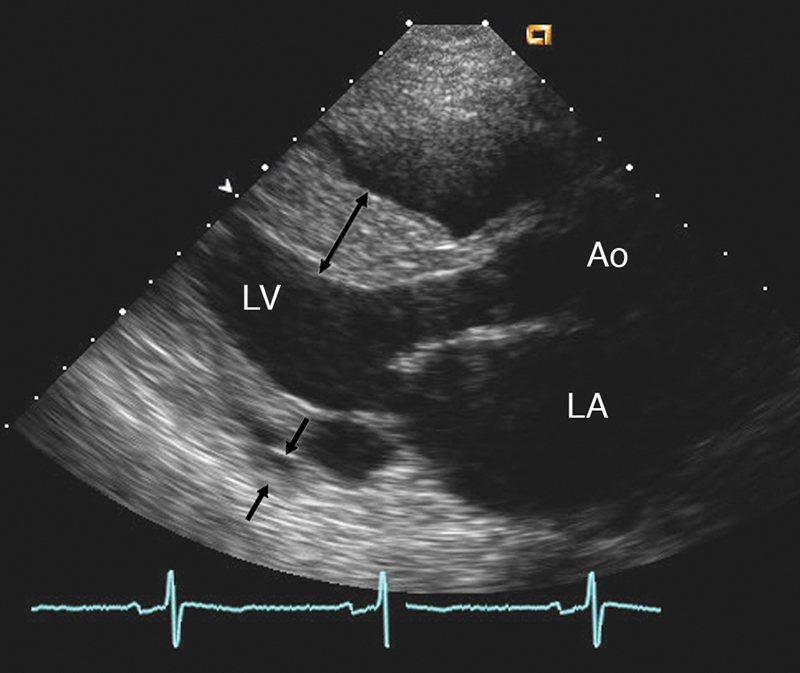

فحوصات تشخيصية لبعض امراض القلب والشرايين التاجية